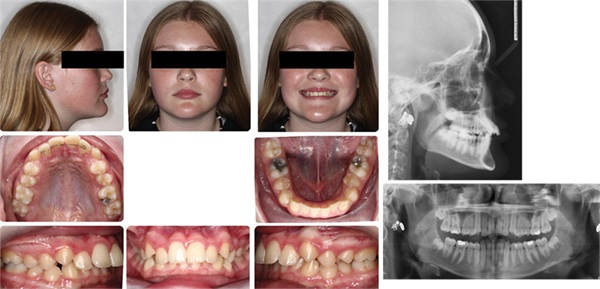

I treated 26-year-old Tara in 2018. Her chief complaint was the unaesthetic appearance of her flared upper teeth. Comprehensive treatment with braces, along with extraction of upper first bicuspids, allowed us to meet our goals in 23 months. Tara was very happy at the end of her treatment. Her lifelong insecurity about her unaesthetic flared upper teeth was completely resolved. Additionally, her teeth were straight, and she had a well-functioning occlusion (Figs. 1–4).

On assessment of my pre- and post-treatment records, I was also satisfied with many aspects of the case, including the alignment, occlusion, overjet reduction, aesthetic arch width, and aesthetic vertical position of the maxillary incisors within the smile. I felt good about the mini-aesthetic (smile) and micro-aesthetic (dental) outcome.

Fig. 1

Late into Tara’s treatment in 2020, I had just begun looking at my cases from an “outside-in” perspective, with an emphasis on prioritizing macro-aesthetic facial features when evaluating all pre-treatment and post-treatment records. This was in large part because of my lengthy time away from practice during the COVID-19 shutdown, which allowed me to read Dr. David Sarver’s book Dentofacial Esthetics: From Macro to Micro. It’s the only book I’ve ever read that I immediately began rereading after finishing.

With a new perspective, I evaluated Tara’s treatment outcome. While I was still satisfied with many aspects of the final results, I was not nearly as happy with the subtle but noticeable change to her soft-tissue facial profile, particularly her lips and circumoral presentation. The amount of incisor retraction achieved through our treatment was more than enough to address the chief complaint of flared teeth, but it also, in my view, went a bit too far in reducing the fullness and forward position of her lips.

Yes, some degree of lip retraction was indicated based on the mild lip incompetence shown in the pretreatment records, but it seemed to me that I had overshot it. Outside of just the lips, her circumoral volume also seemed more deflated or sunken. Her final photos show more pronounced nasolabial folds, downward lateral commissures, and the appearance of marionette lines. Additionally, her chin projection, because of her retracted lips, now appeared relatively more forward. To me, the treatment that took two years appeared to have taken 10 years.